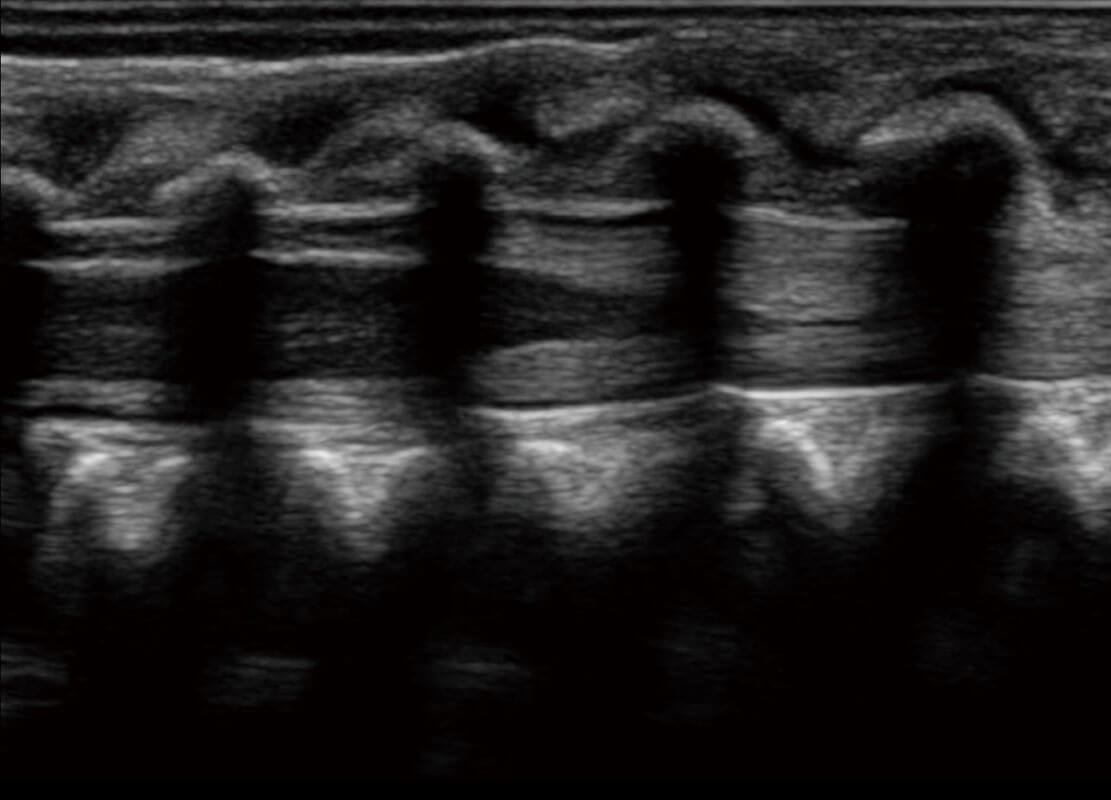

P60为盆底超声检查提供应用方案,多种腔内及腹部容积探头提供从二维、三维到四维的优异图像品质,实时快速三维容积数据获取,专业的测量工具包等人性化设计,为超声医生诊断提供有力保障。

Lev.Hiat A-r: 16.33 cm2

Lev.Hiat H-r: 53.70 mm

Lev.Hiat W-r: 43.96 mm

Lt-LUG-r: 24.16 mm

Rt-LUG-r: 19.94 mm

能够简化盆底检查的操作流程,可在二维模式及三维成像模式下实现一键自动提取出标准切面、自动识别当前切面、自动测量,提升盆底检查的高效性,同时也能让青年医生快捷的获得准确的检查结果。